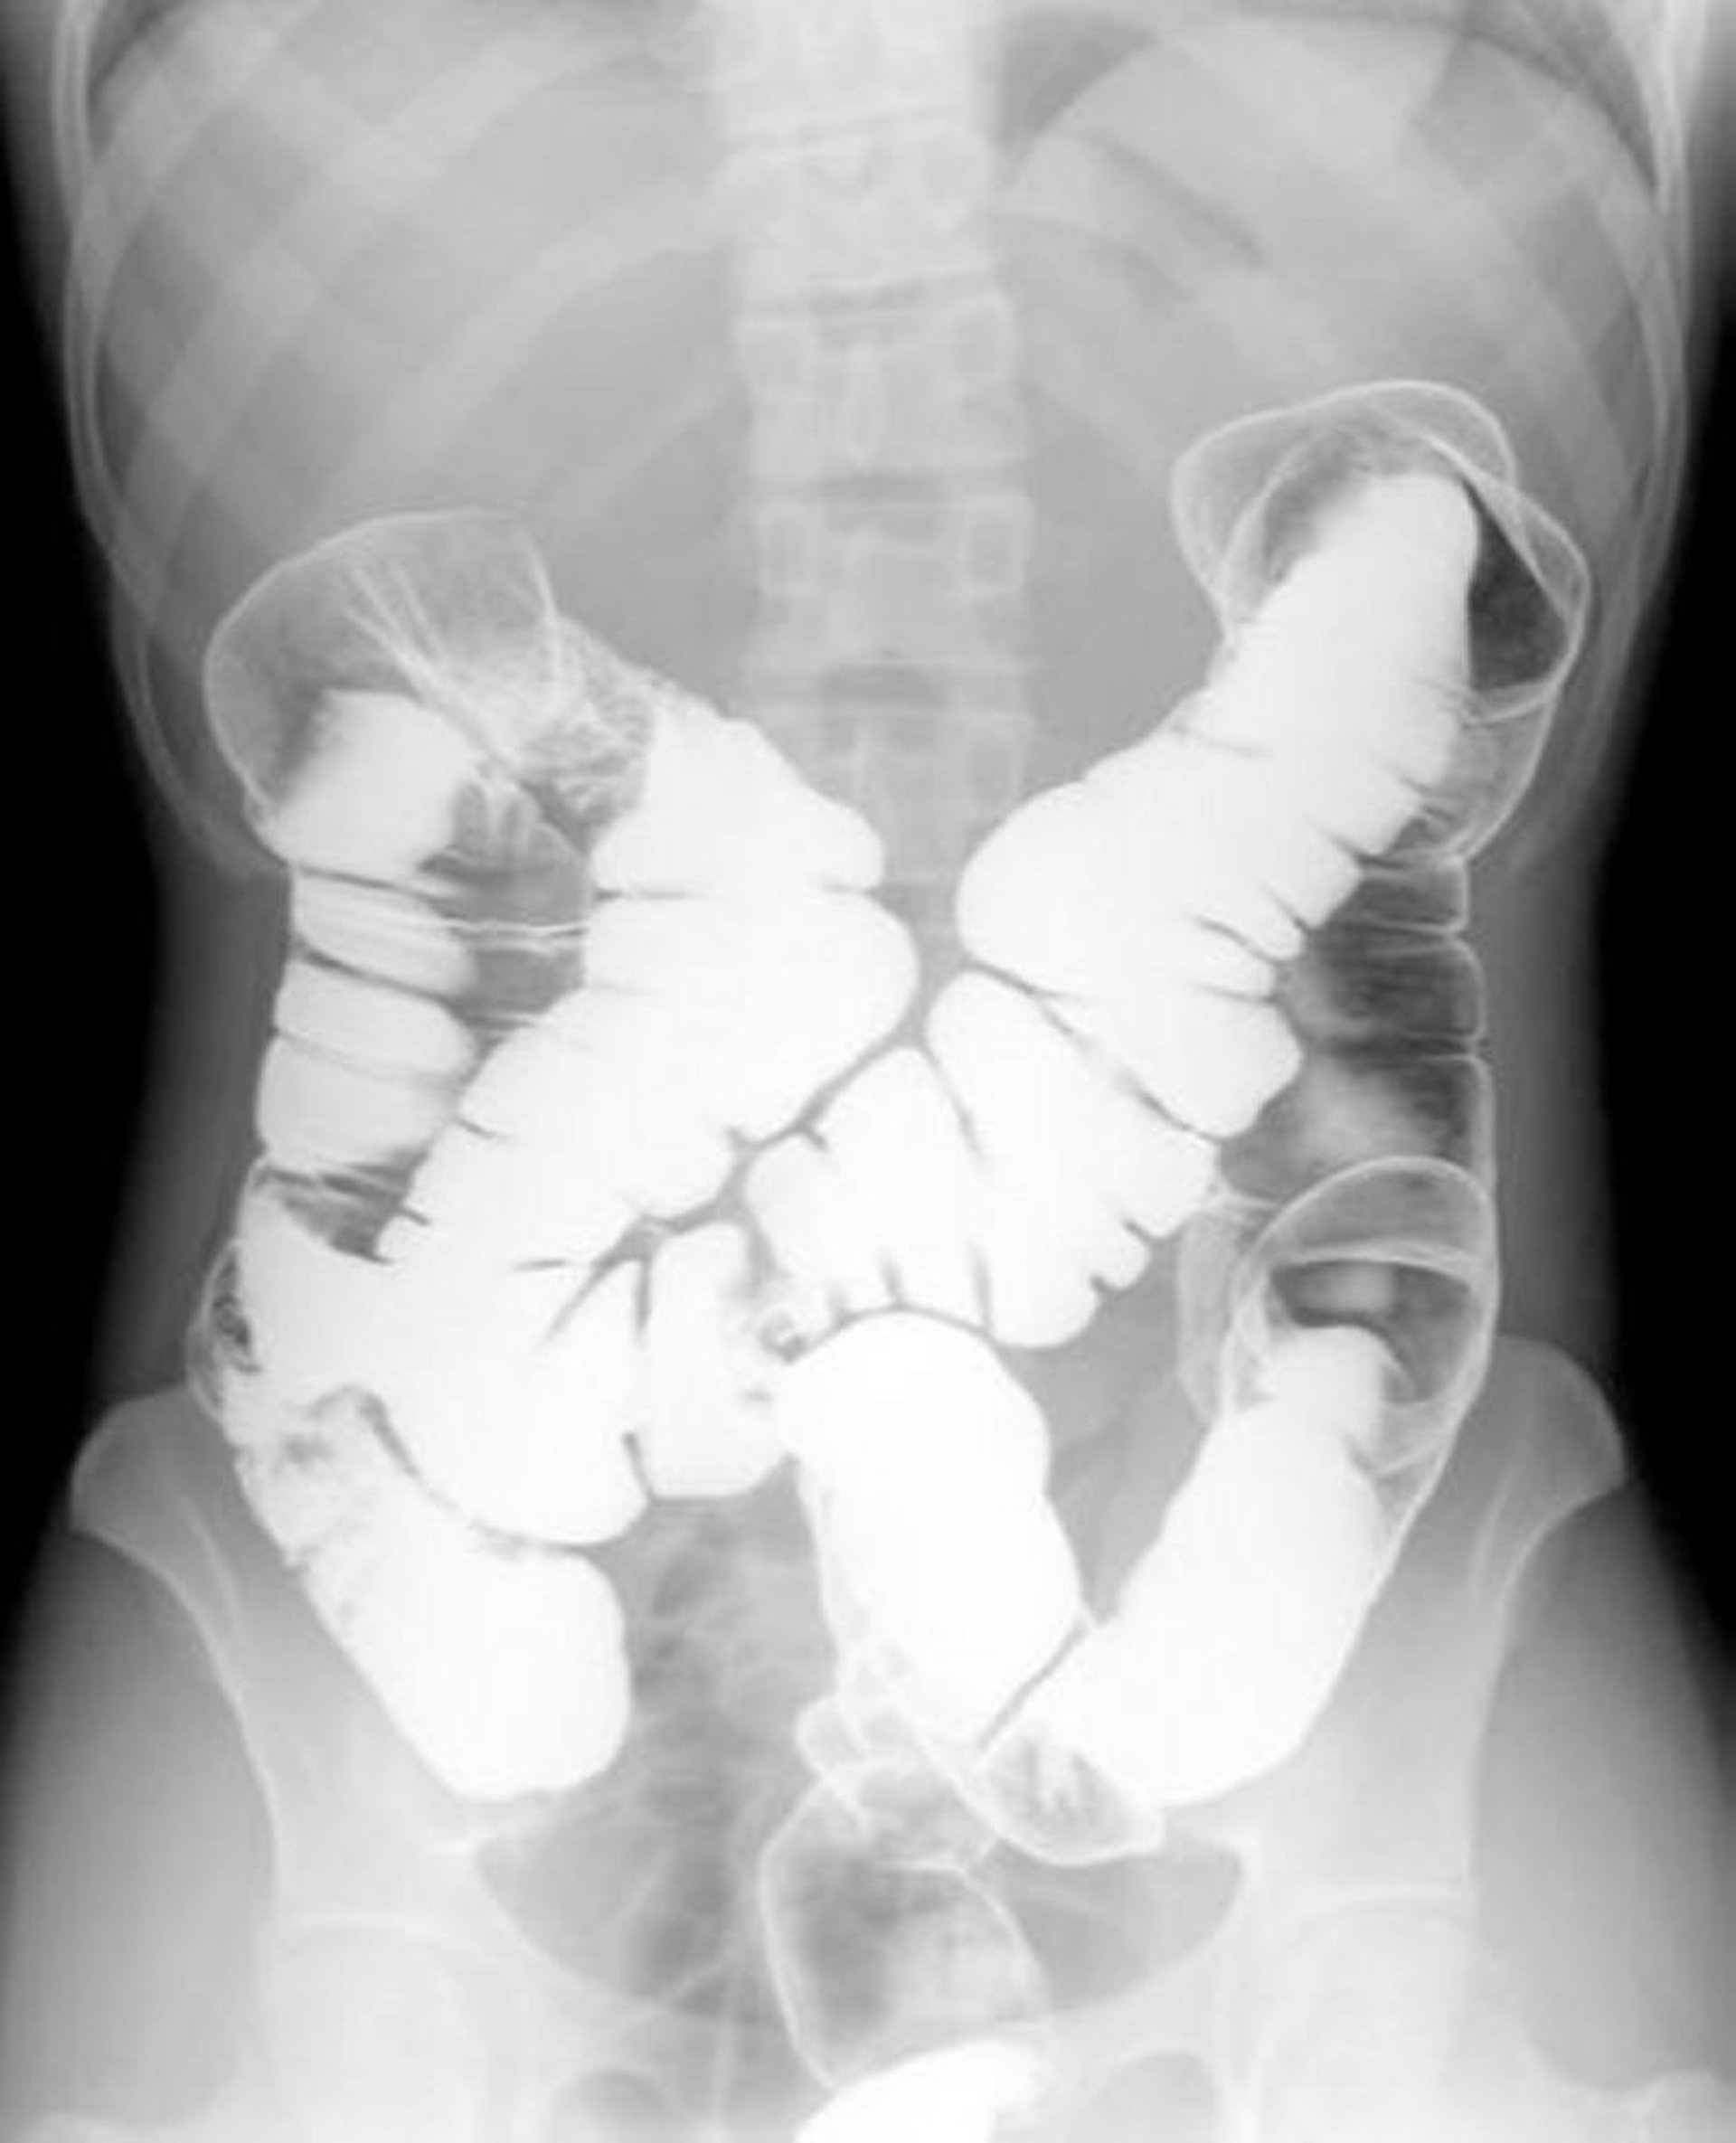

Enema de bario con doble contraste que muestra anatomía normal

Esta imagen muestra el patrón de aire y bario dentro de un colon normal.